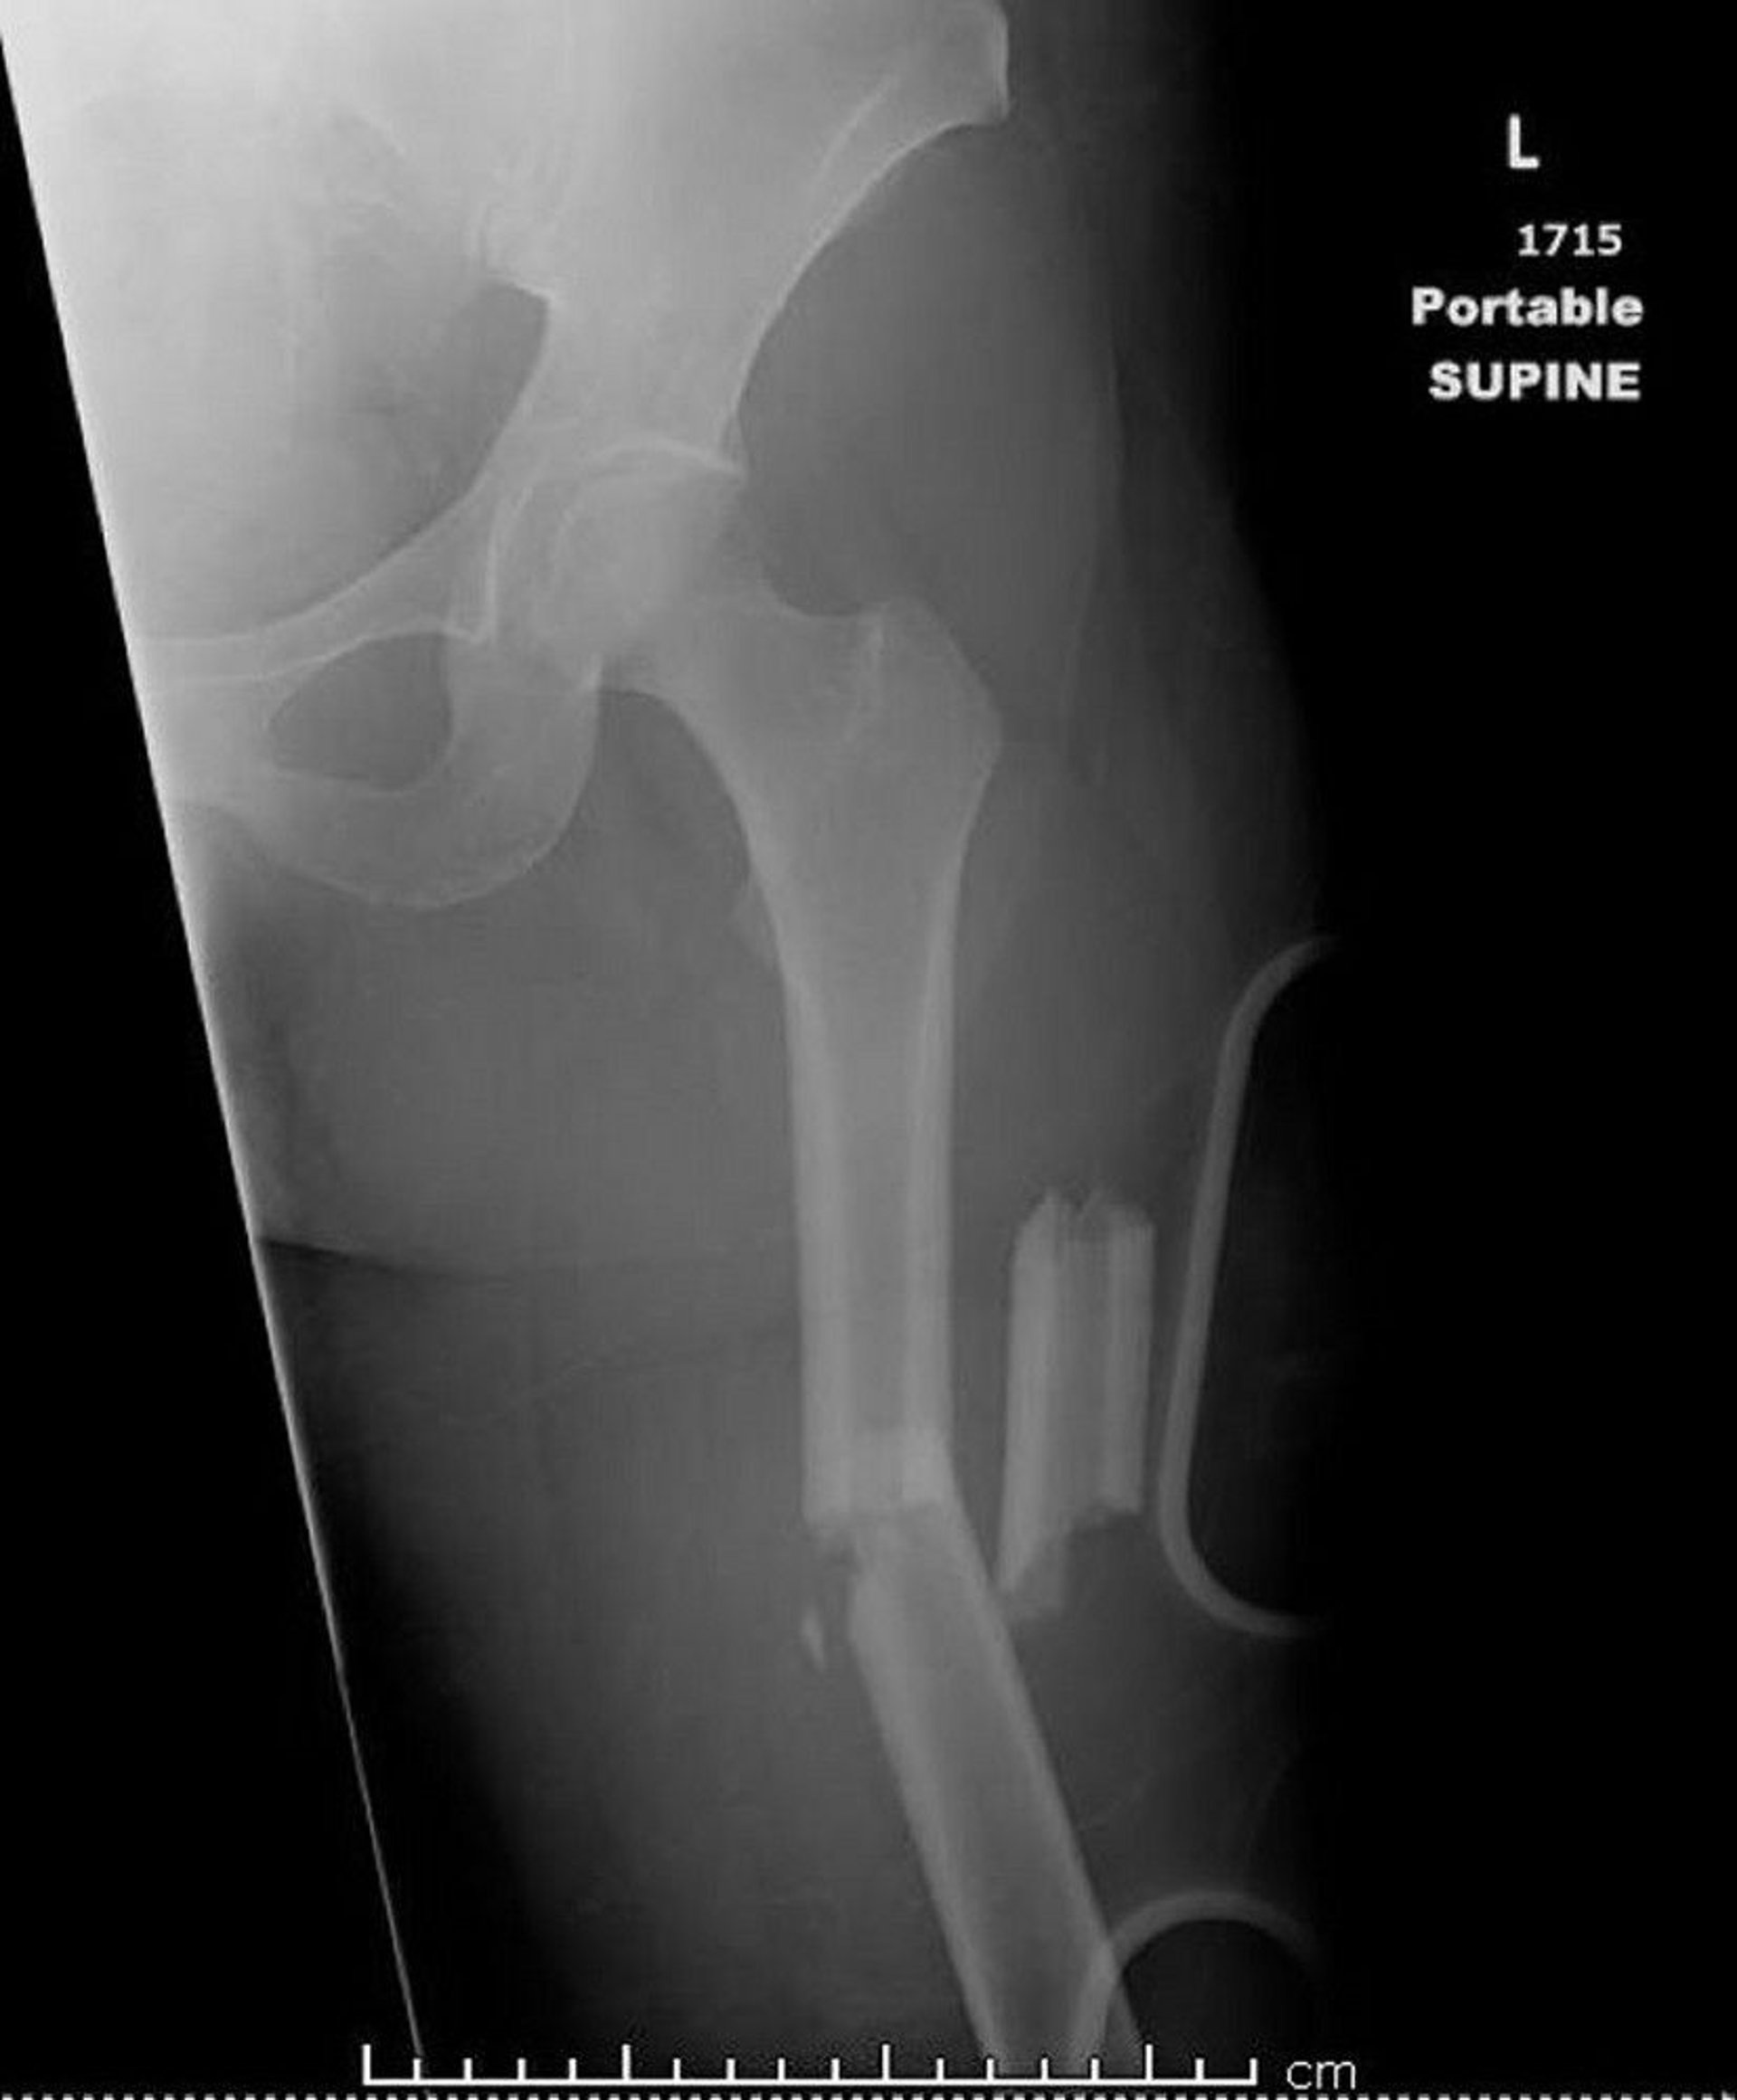

Midshaft Femur Fracture (1)

This image shows a comminuted, angulated, and shortened midshaft femur fracture.

Image courtesy of Danielle Campagne, MD.